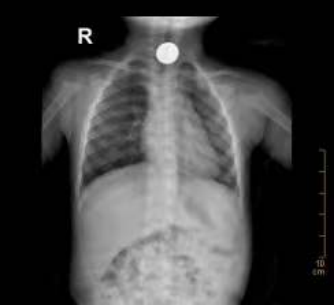

经胸片检查,小宝食管上段存在一圆形大小约20X20mm金属异物,很明显就是硬币。

小宝食管上段存在一圆形大小约20X20mm金属异物